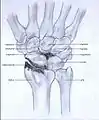

Stages

Post-traumatic osteoarthritis can be classified into four stages.[1][7] These stages are similar between SLAC and SNAC wrists. Each stage has a different treatment.

- Stage I: the osteoarthritis is only localized in the distal scaphoid and radial styloid.

- Stage II: the osteoarthritis is localized in the entire radioscaphoid joint.

- Stage III: the osteoarthritis is localized in the entire radioscaphoid joint with involvement of the capitolunate joint.

- Stage IV: the osteoarthritis is located in the entire radiocarpal joint and in the intercarpal joints. It also may involve the distal radio-ulnar joint (DRUJ).

Stage I

Stage II

Stage III

Stage IV